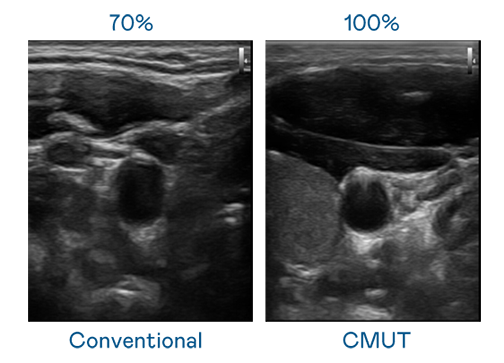

CMUT 技术是一种用电容式微机电元件来产生超音波讯号的技术。与传统 PZT 压电式技术相比,CMUT 频宽增加 30%,更宽频的超音波讯号让影像解析度大幅提升,是实现高影像品质医疗超音波扫描、促进精准医疗发展的关键技术。

大频宽带来超清晰影像

超音波影像的解析度高低,首先取决于探头能发出的讯号频宽。俄罗斯专享会全民vip CMUT 可提供高清晰的超音波讯号,提供高频宽、高灵敏度、影像纹理细节更高的超音波影像,协助医护人员缩短影像判读时间及利用精准的医疗影像进行诊断。